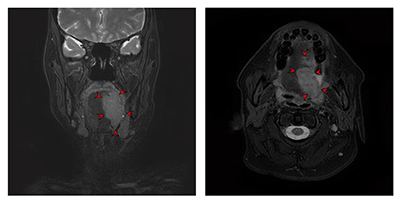

전산화단층촬영(CT)과 더불어 임상적 병기 결정을 위한 정보를 얻는데 사용합니다. 연조직에 발생한 암종의 경우 자기공명영상이 더 선호되고 있어 설암 환자의 경우 자기공명영상이 필수적이라 할 수 있습니다. 촬영 전 구강 내 보철물은 제거하고 촬영하는 것이 상의 왜곡을 막기 위해 필요합니다.

[ 좌측 설암의 자기공명영상 촬영 이미지 ]